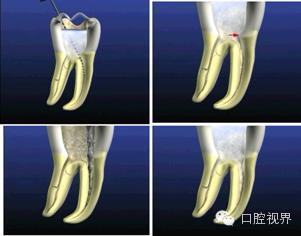

根管治疗 ( 根管预备和根管充填 ) 有多种方式,根据现有的知识和器械材料,本着高质量、快速度、低消耗的原则,设定了一种常规的根管治疗术式。

根管治疗包括根管预备、根管冲洗和根管充填。本节将介绍根管预备。

根管预备是通过机械方式配合化学药物去除、清理根管里面的污染物,使根管成为一定形态,利于冲洗和充填。

根管预备需开髓孔大小标准的确认的基础上,应注意根管预备的形态 ( 便宜形态 保持形态 抵抗形态 ) 。